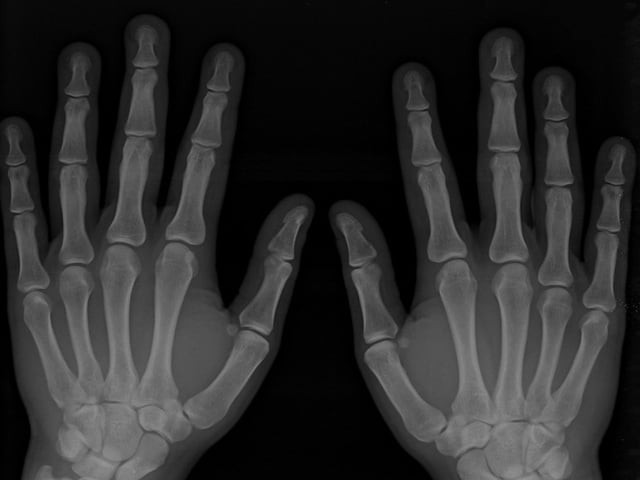

Artificial intelligence (AI) could significantly reduce missed fractures on X-rays, according to the National Institute for Health and Care Excellence (NICE), which endorses AI technology as a support tool for NHS clinicians.

NICE's research indicates that integrating AI into urgent care for X-ray analysis can enhance the accuracy of fracture diagnoses, especially as it helps identify cases that might otherwise be overlooked due to high clinical demands.

AI is expected to fill part of this gap, providing clinicians with an extra set of ‘eyes’ to spot fractures accurately. According to NICE’s health technology director, Mark Chapman, the AI tools can improve diagnosis rates and lessen follow-up appointments for fractures missed during initial assessments.